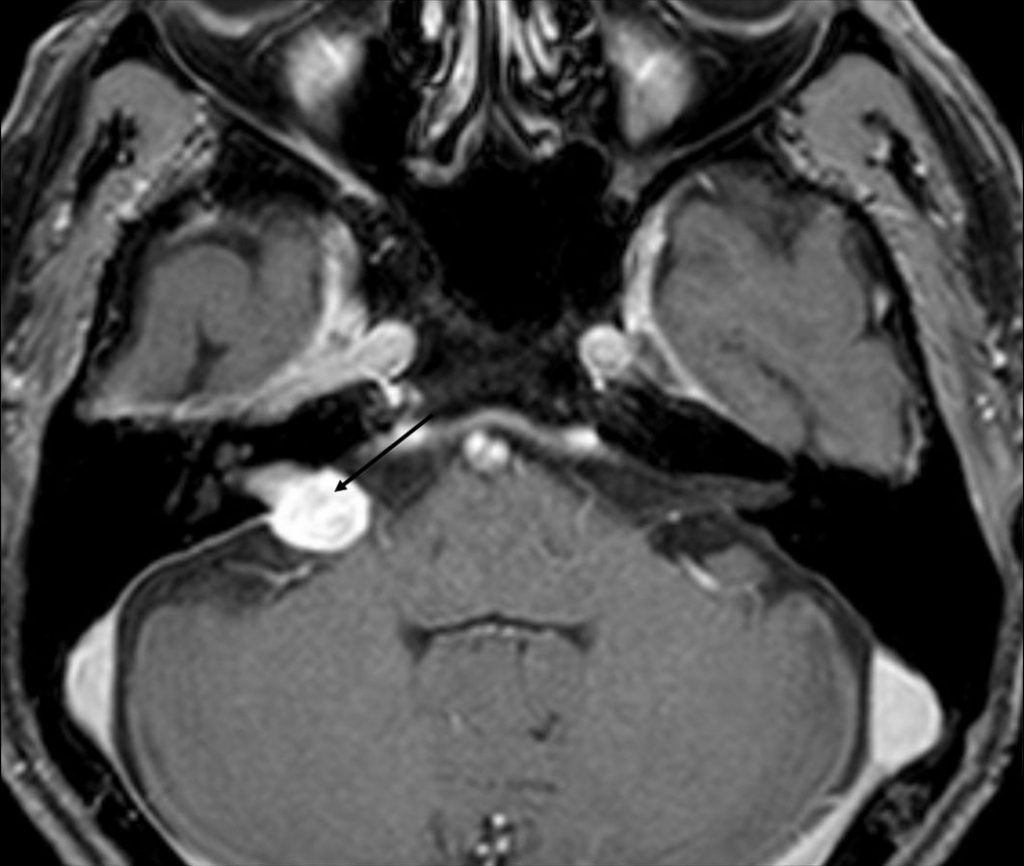

Fig. 64.3 Schwannome vestibulaire.

IRM en coupe transversale en T1 après injection de produit de contraste : tumeur centrée sur l’angle pontocérébelleux et le méat acoustique interne (flèche) avec prise de contraste intense.

La pathologie la plus fréquente est le schwannome vestibulaire (neurinome de l’acoustique) (figure 64.3). Il se manifeste par :

une tumeur bien limitée extra-axiale de l’angle pontocérébelleux, centrée sur le méat acoustique interne présentant un angle de raccordement aigu avec la face postérieure de la partie pétreuse de l’os temporal ;

- un élargissement fréquent du méat acoustique interne ;

- une prise de contraste intense et souvent homogène ;

- un extension extraméatique possible pouvant entraîner un effet de masse sur le tronc cérébral, voire une hydrocéphalie par compression du quatrième ventricule.